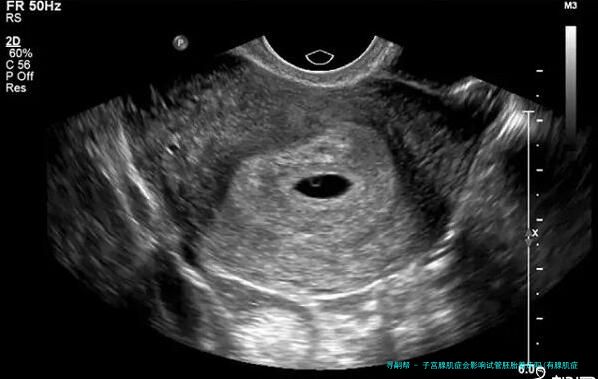

要知道,有很多性友人都患有子宫腺肌病,因此生育受阻。此外他们在长远治疗后择了试管来辅助怀孕,这也正是他们问第一个问题的缘故。如此到底什么是子宫腺肌病呢?据这个专业人士讲解,子宫腺肌病是一种多见的妇科疾病,主要是缘由是子宫内膜腺器官和间质侵入子宫肌层,造成弥漫性或局限性病变。患病人群多为30-五十岁的经产妇(即生过1个以上孩子的性),但年少的没有子女性也有机会患病。

子宫腺肌病会导致试管婴儿的成功率下降,因为在子宫腺肌病的影响下,子宫内膜会移位,引发炎症反应,子宫变大,强化了子宫的收缩功能,因而会影响胚胎的着床。很多条件下,即使胚胎植入成功,后期流产率也会高于正常人。因而想做试管婴儿的性朋友可以先做相关治疗,再做试管婴儿,以免影响试管婴儿的成功率。

子宫腺肌病可以表现为1个坚硬的结节。子宫腺肌病较重的情况会像个球,导致子宫增大,质地松垮,活动本领差。统计表现,百分之十五~40%的子宫腺肌病会并发子宫内膜异位症,约对折患者会并发子宫肌瘤。因此要是不经处置直接移植胚胎,会影响胚胎的着床,降低性的怀孕率。因而关于患了子宫腺肌病的性,建议先进行试管婴儿的诊断和治疗,痊愈后再进行移植,如此成功率更高,好孕率更有保证。大家周知,子宫内膜是胚胎最终着床发生育之处,是保证着床成功率的基础。而且子宫腺肌病会直接影响子宫内膜的质量和宫内环境,所以自然会妨碍胚胎着床。